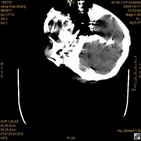

术后46小时复查CT

术后46小时复查1 术后46小时复查2 术后46小时复查3 术后46小时复查4